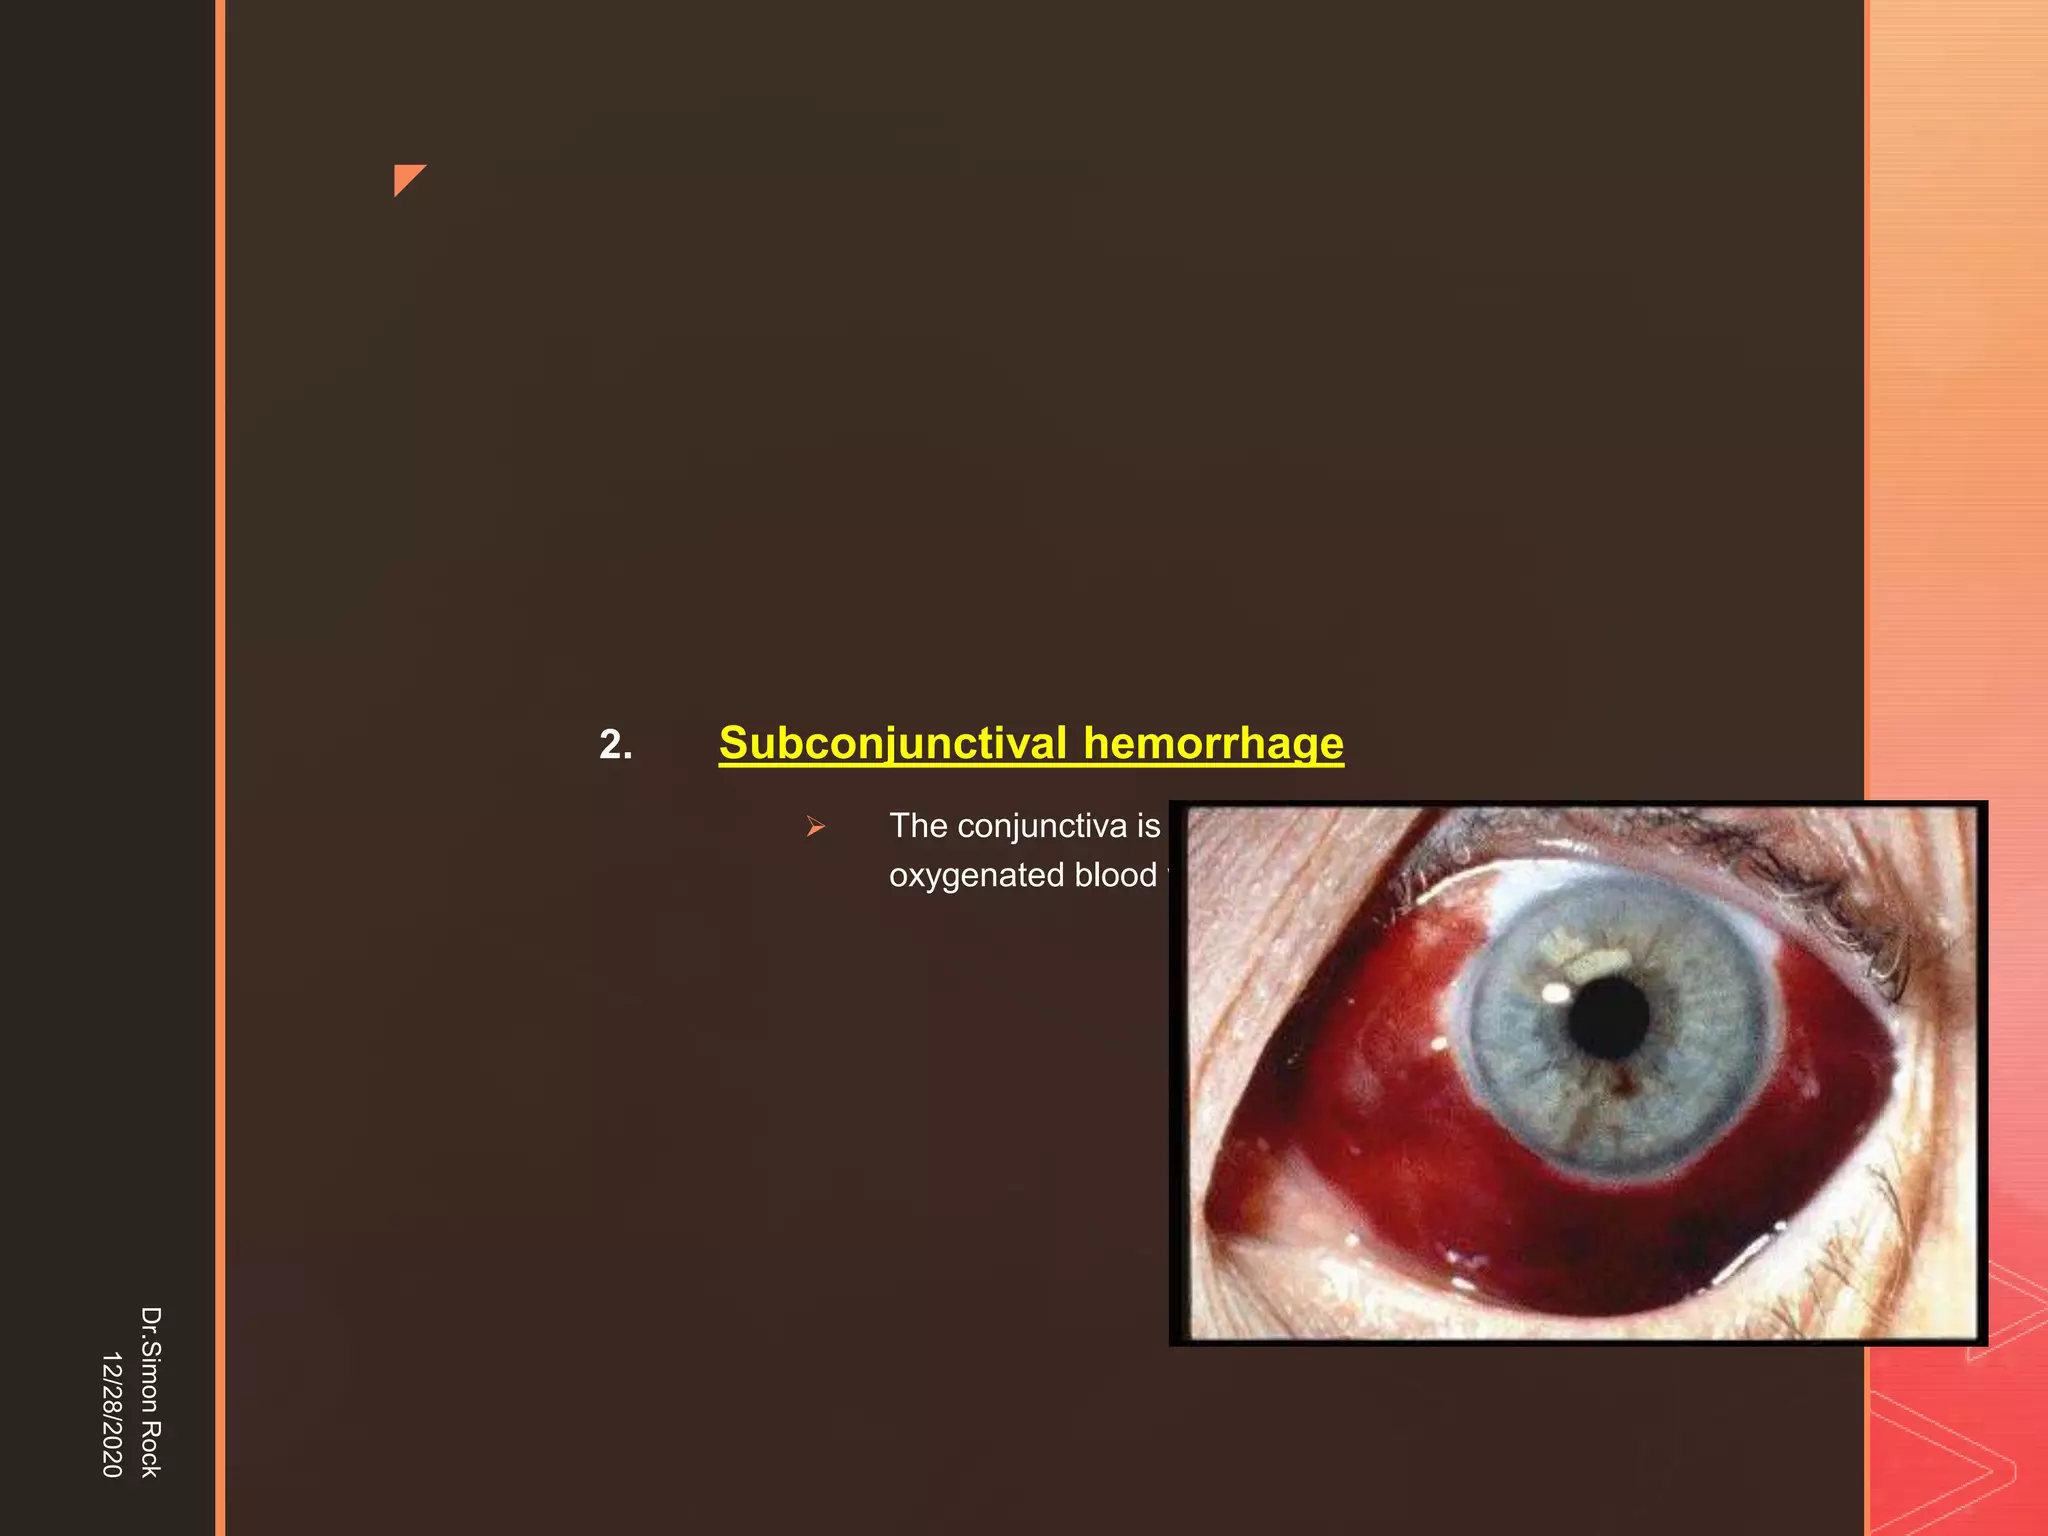

This document discusses the anatomy and fractures of the zygomatic bone. It notes that the zygoma forms the cheekbone and articulates with several other facial bones. Zygomatic fractures most commonly occur in the arch or body due to blunt trauma. Diagnosis involves checking for diplopia, ecchymosis, and other signs of orbital or facial bone involvement. Treatment may involve closed or open reduction based on the severity of displacement. Closed reduction techniques try to elevate the bone back into position without surgery, while open reduction requires surgical exposure and fixation of the fracture site.